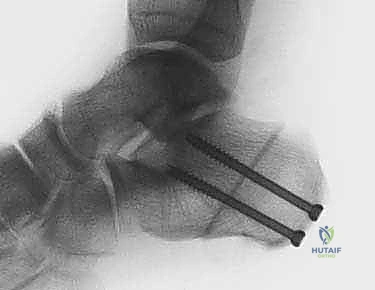

لذلك، يقوم الأستاذ الدكتور محمد هطيف بإجراء "قص عظم الكعب" أولاً لتغيير محور تحمل الوزن في القدم. من خلال إزاحة عظم الكعب إلى الداخل (إنسياً)، يتم نقل قوة شد وتر أخيل لتساعد في رفع القوس بدلاً من تسطيحه. هذا الإجراء العظمي يحمي الوتر المنقول الجديد (FDL) ويمنحه البيئة الميكانيكية الصحيحة ليعمل بكفاءة مدى الحياة.

الخطوة الأولى: قص وتعديل عظم الكعب (MDCO)

هذه هي الخطوة التأسيسية لإصلاح الميكانيكا الحيوية للقدم.

1. الشق الجراحي: يتم عمل شق جراحي صغير (حوالي 3-5 سم) على الجانب الخارجي للكعب، مع الحرص الشديد على حماية العصب الربلي (Sural nerve).

2. قص العظم (Osteotomy): باستخدام منشار